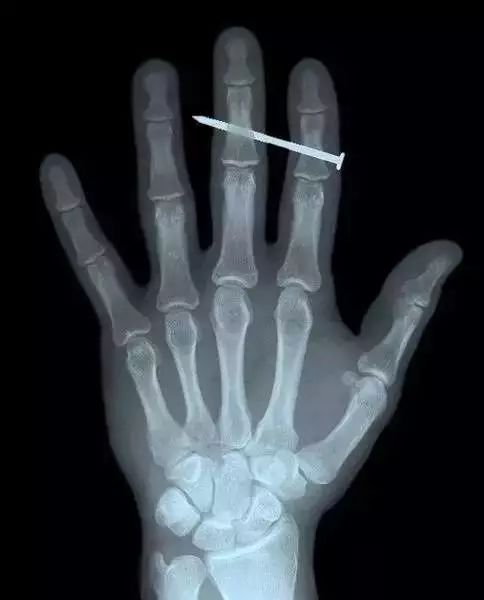

15、这张X光片上,这个成年男性的中指被一根钉子穿透。